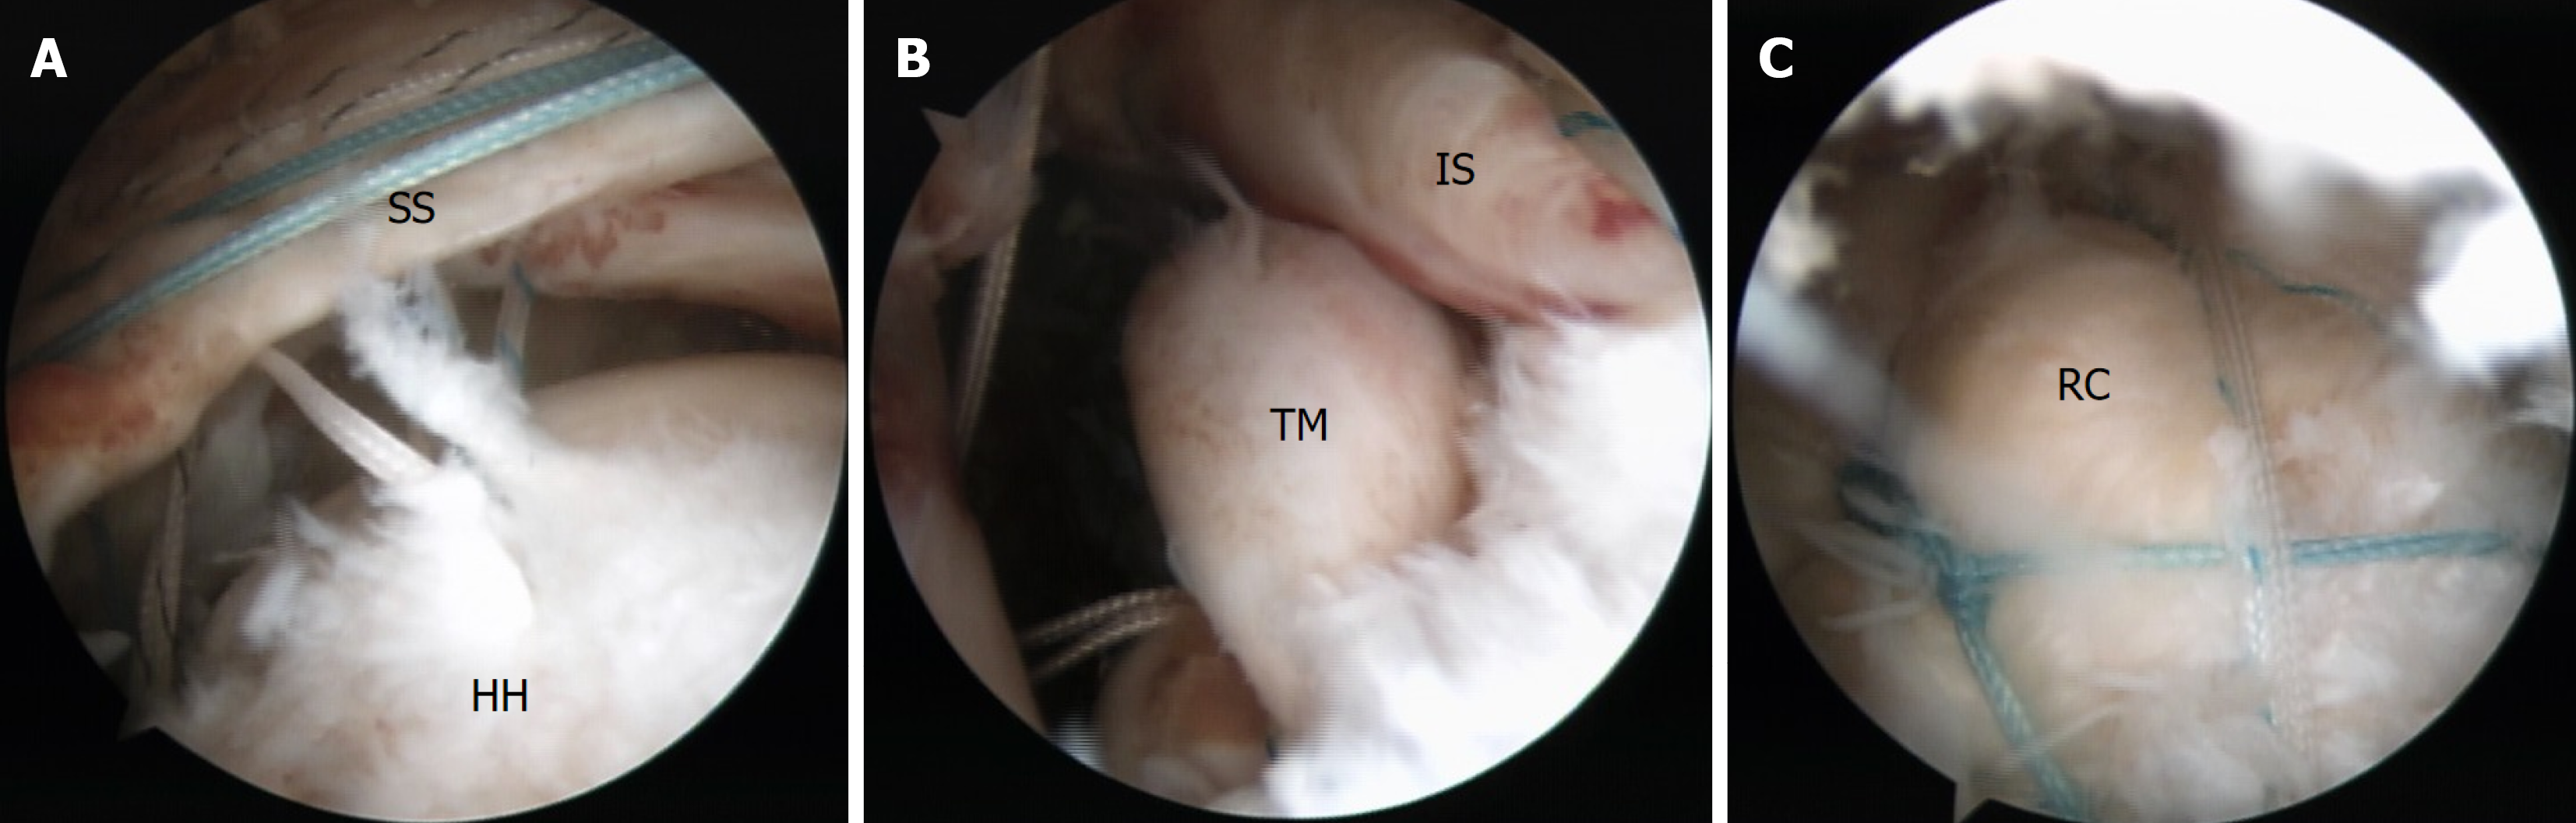

Figure 5 Arthroscopic view of the complete tears.

A: Torn supraspinatus tendon; B: Torn infraspinatus tendon. In the subacromial space after the acromioplasty, debridement, bursectomy, and release of the torn rotator cuff, complete tears of the supraspinatus and infraspinatus tendons were confirmed. The teres minor remained relatively intact. SS: Supraspinatus; HH: Humeral head; IS: Infraspinatus; TM: Teres minor.

Figure 6 Rotator cuff repair using a suture bridge technique.

A and B: Three double-loaded suture anchors were evenly placed at the medial aspect of the rotator cuff footprint, and the torn tendons were sutured using a horizontal mattress technique; C: All sutures were crossed and secured to a lateral anchor. SS: Supraspinatus; HH: Humeral head; IS: Infraspinatus; TM: Teres minor; RC: Rotator cuff.